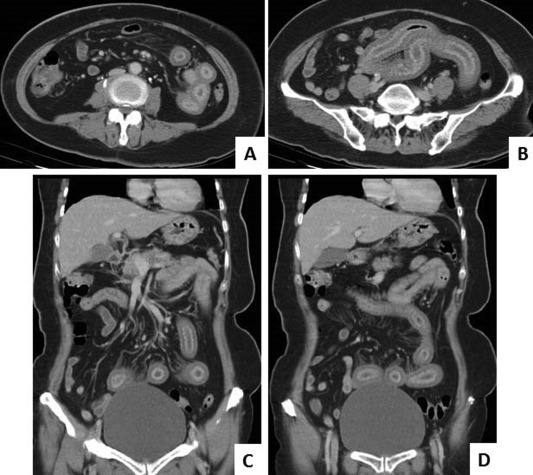

A 59-year-old woman with hypertension and DM presented with progressive abdominal pain over the upper abdomen. Esophagogastroduodenoscopy, colonoscopy, and transabdominal ultrasonography revealed no significant findings. Contrast-enhanced abdominal computed tomography revealed segmental small bowel wall thickening (∼1.0 cm in thickness) with fair mucosal enhancement and engorged mesenteric vessels (Figure 3 ). The small bowel follow-through showed continuous mucosal irregularity and thickening extending from the proximal jejunum to ileum. SBE (SIF-Q260) with ST-SB1 splinting tube (Olympus Co.) via the antegrade approach was performed and showed diffuse irregularly-shaped ulcers with exudative coating and geographic distribution extending from the upper to middle jejunum (Figure 4 ). Biopsy was performed and histopathology showed mucosa ulceration with several nuclear inclusion bodies and positive CMV immunoreactivity (Figure 5 ). CMV jejunitis was confirmed. The serum CMV immunoglobulin-M antibody was negative, immunoglobulin-G antibody was positive, and the serum viral load test detected CMV viremia (2280 copies/mL). Both autoimmune profile and HIV screening test were negative. Antiviral therapy with ganciclovir (250 mg every 12 hours) for 10 days was prescribed, followed by oral valganciclovir (900 mg/d) for 1 month. Her abdominal pain subsided gradually and subsequent serum CMV viral load was undetectable.

(A, B) Coronal view of contrast-enhanced computed tomography reveals segmental ...

Figure 3.

(A, B) Coronal view of contrast-enhanced computed tomography reveals segmental small bowel wall thickening with fair mucosal enhancement; (C, D) sagittal view of contrast-enhanced computed tomography also reveals small bowel wall thickening with engorged mesenteric vessels.